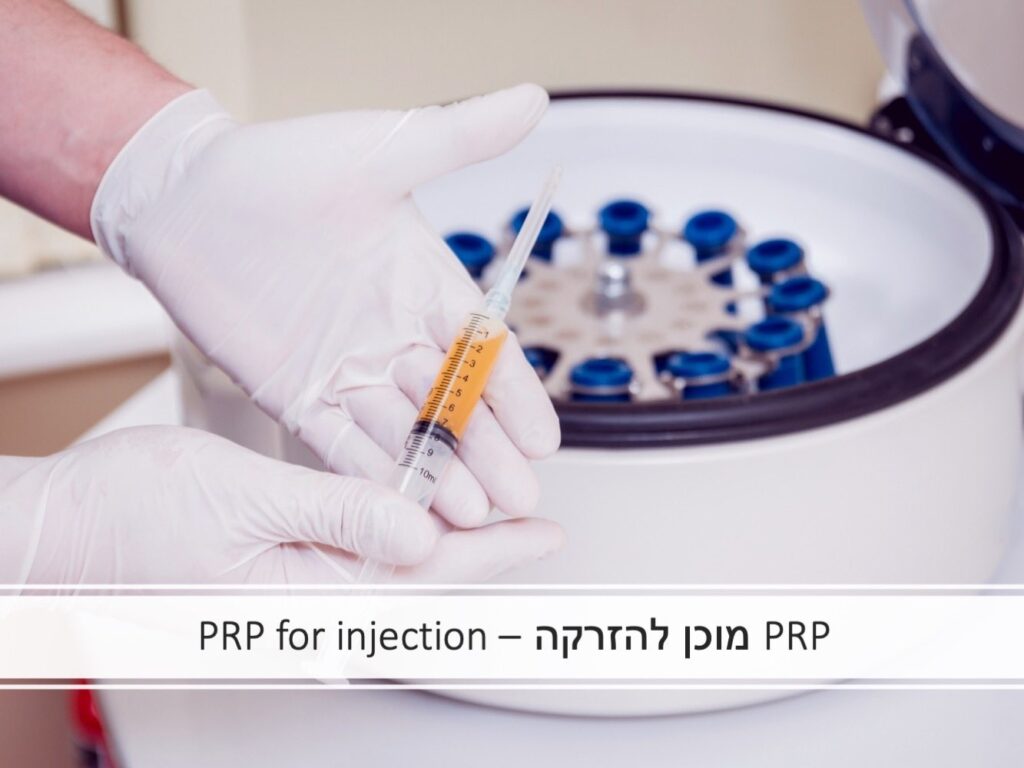

המוצר הביולוגי הנחקר ביותר והנפוץ ביותר בשימוש כיום הוא ה-PRP (Platelet Rich Plasma) – פלסמה (פלזמה) עשירת טסיות. מדובר בתוצר דם עצמי (הנלקח מהמטופל כבדיקת דם רגילה) המכיל, לאחר תהליך הכנה, ריכוז גבוה של טסיות. פלסמה (פלזמה) היא נוזל הדם והטסיות הן אחד ממרכיבי הדם והן בעלות תפקיד חשוב בתהליך הקרישה שנועד להגן על הגוף מדימומים.

PRP - שלבי ההכנה העיקריים:

- לקיחת דם מהמטופל (בדיקת דם רגילה לחלוטין).

- המבחנה והדם בתוכה עוברים תהליך סרכוז (צנטריפוגציה) בצנטריפוגה. תהליך זה מאפשר הפרדה של מוצרי הדם.

- הוצאה מבוקרת וסטרילית של החלק במבחנה בו נמצאות הטסיות שהופרדו משאר מרכיבי הדם.

- הזרקה של פלסמה עשירה בטסיות (PRP) אל הרקמה/המפרק המיועד בתנאים סטריליים.